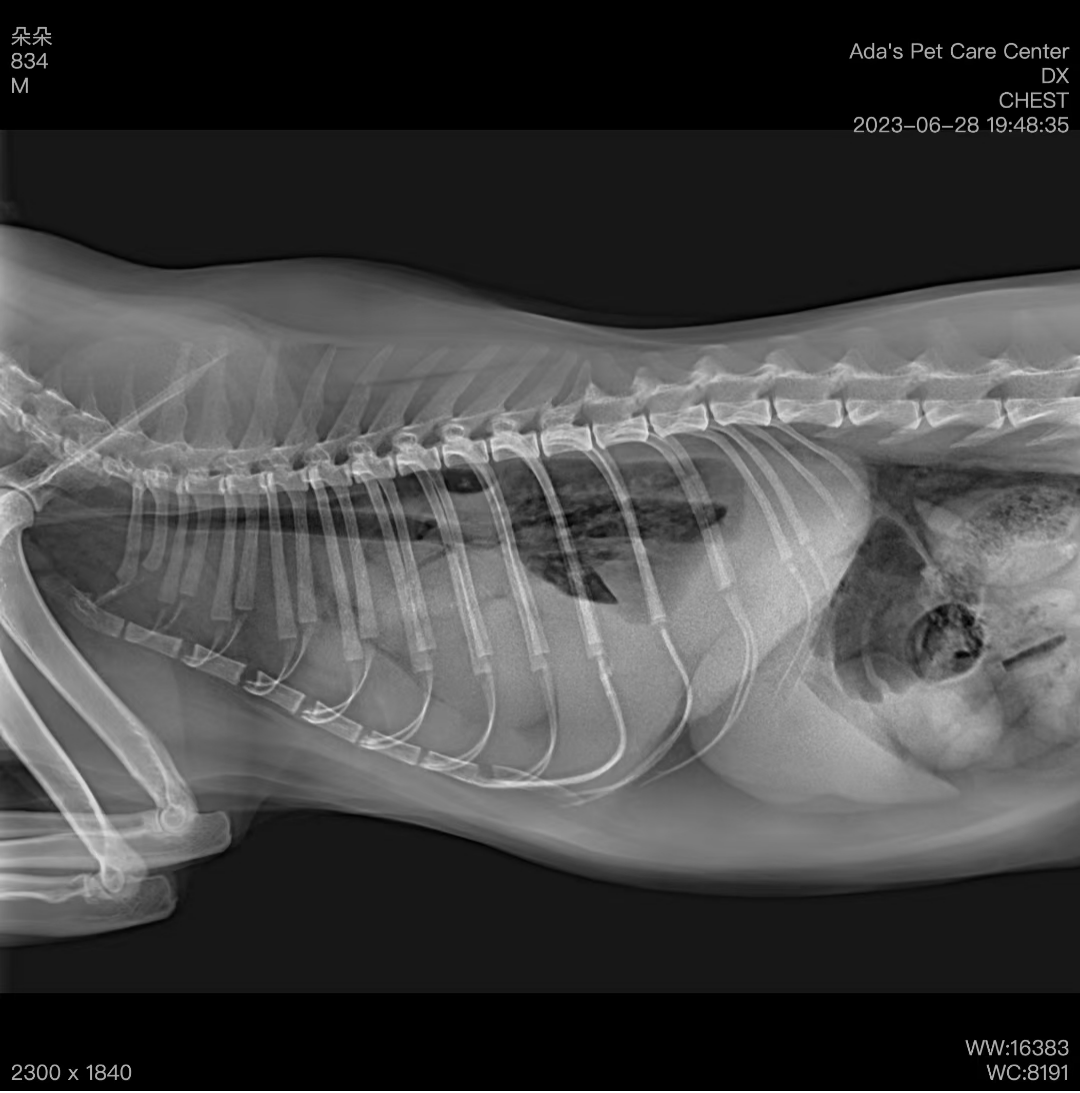

When the cat arrived, it was lethargic, struggling to breathe, and its tongue was purple. After oxygen therapy, its breathing improved slightly. We took an X-ray of the chest, which showed significant fluid buildup. We then performed a chest tap and drew about 200ml of yellowish fluid. After analysis, it was confirmed as chylothorax.